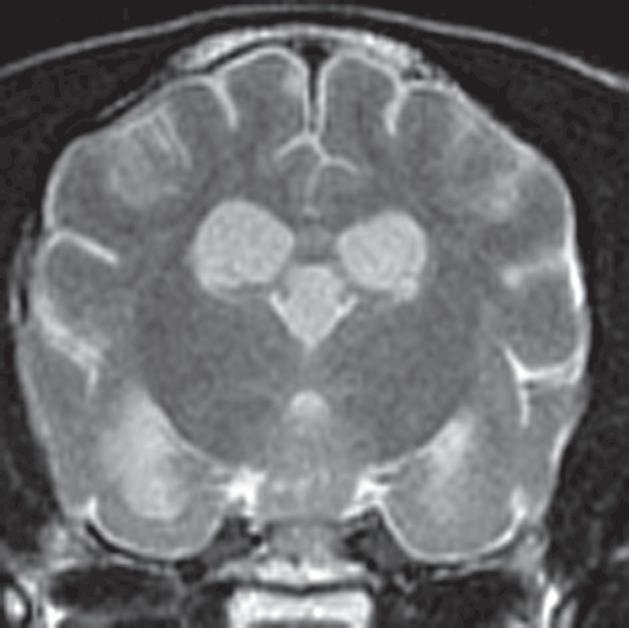

Rycina 2.9.12. Gruczolak przysadki (pies) MR

Badanie wykonano u 14-letniej, kastrowanej samicy szpica z przechyleniem głowy i występującym od niedawna chodzeniem w kółko w prawą stronę. Ryciny a–c to reprezentatywne obrazy w płaszczyźnie poprzecznej na poziomie dołu przysadki. Ryciny d–f to analogiczne obrazy w płaszczyźnie strzałkowej. Przysadka mózgowa była znacznie powiększona (wysokość = 10 mm, szerokość = 10 mm), izointensywna w obrazach T1-zależnych (a, d) i łagodnie hiperintensywna w obrazach T2-zależnych (b, e) w porównaniu z istotą szarą głęboką. Stwierdzono również poszerzenie układu komorowego (wentrikulomegalię), które może wynikać z częściowej niedrożności. Przysadka uległa jednorodnemu wzmocnieniu kontrastowemu (c, f), a w badaniu pośmiertnym wykazano, że miała postać dobrze odgraniczonej, kulistej masy (g). Potwierdzono, że zmiana była makrogruczolakiem przysadki